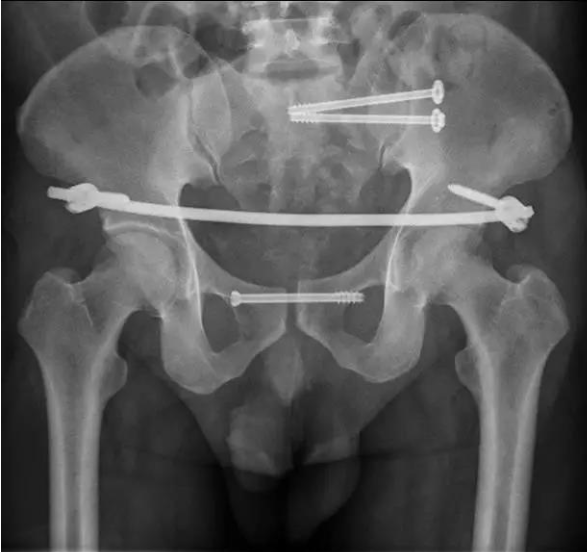

近日,潍坊市人民医院创伤骨科二区开展复杂骨盆骨折闭合复位微创经皮内固定手术治疗一例复杂不稳定型骨盆骨折患者。该手术时间短、创伤小、出血少,进一步拓展了潍坊市人民医院复杂骨盆骨折手术治疗的新手段。

患者中年男性,肥胖体型,由约 18 米高处坠落,因伤势严重转入潍坊市人民医院创伤骨科二区,经检查诊断为「骨盆粉碎性骨折、骶骨纵行粉碎骨折、耻骨联合分离、腰椎骨折」,骨盆极度不稳定。

创伤骨科二区张培良团队查阅国内外文献及对解剖标本、透视体位等进行了分析讨论,由孙学成带领手术小组按照术前计划,在麻醉科大力配合支持下行骨盆后环闭合复位骶髂螺钉固定、前环耻骨联合行空心螺钉固定、髂前下棘内固定支架进一步稳定骨盆环。手术顺利,病人恢复良好。